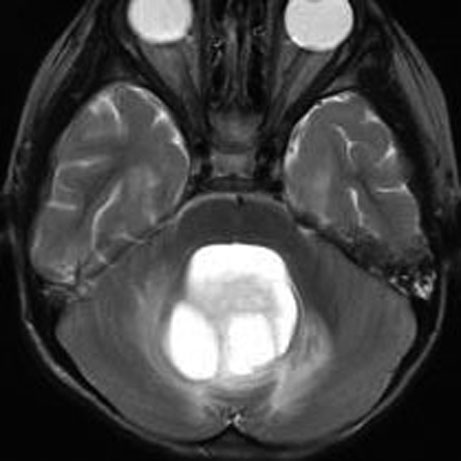

4歳発症の大きなもの

これも小脳中部上端から発生したもので,中脳水道が開いています。OTAで摘出しなければ小脳中部に大きな損傷を与えるものですから,後頭下開頭をしてはなりません。術後10年ほど経ちますが再発はなくてダンスをしてます。